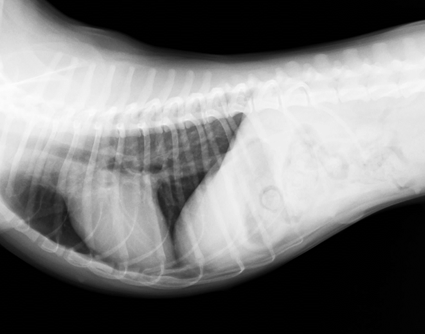

飼い主様のご希望で検査を行ったところ、肝酵素の上昇とレントゲンにて肝臓の大きさが小さく、小肝症と診断しました。追加検査にて測定した総胆汁酸が食前、食後ともに正常値をはるかに上回る数値だったため先天性疾患である門脈体循環シャントといわれる病気が強く疑われました。

小肝症